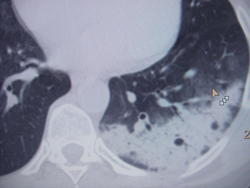

Деструктивная пневмония, тб?

Медработник, находится на стац лечении в терап.отд по поводу двусторонней полисегментарной  пневмонии с 14 августа. Получила курс а/б терапии 2 мя антибиотиками, на рентгенконтроле через 7 дн- незначит. динамика . Сейчас получает 2й курс - метрогил и таваник в/в кап. Сегодня направили на КТ для исключения специф.процесса. Больше склоняюсь к туберкулезу.

В мокроте мбт (-) 2 кратно микроскопией. Жалобы на одышку, при поступлении явных симптомов интоксикации не было, на фоне герпетич инфекции (лечилась у гинеколога) повышалась температура до 38-39*.  Ваше мнение, уважаемые коллеги?

.... и почему сразу туберкулез, хотя туберкулезное поражение легочной ткани может выглядеть весьма вариабельно, поэтому подозревать  и  исключать его , конечно надо, однако при таком распостранении процесса  мокрота была бы положительна на МБТ.   На мой взгляд маловато сканов представлено..  Какие изменения в крови ?

В правом лёгком есть деформация междолевой плевры, что больше говорит о новообразовании. Медработник, наверное, есть архив. Ведь каждый год флю проходим.

Не умею рисовать. На первом скане изогнутая линия, которая проходит по краю образования, это междолевая плевра. Нижняя доля воздушная, а средняя с "матовым стеклом". Вот эта дуга и есть деформация.

На мой скромный взгляд, справа периферическое новообразование с канцероматозным лимфангитом, а слева - деструктивная пневмония.Есть иммунодефицит, думаю герпетическая инфекция не могла не подкосить, вот и "накрыло"

В анализах: в ОАК при поступлении- Нб 119, СОЭ 42, через 3 дня Нб 117, СОЭ 52,  через 11 дн Нб 115, СОЭ 65.  Сопут д-з опоясывающий герпес в обл анальной складки.

Сегодня в отделении сказали, что вроде муж у неё болел 10 лет назад ТБ, но она об этом молчит, а мне вчера не сознавалась ни о каких- либо семейных контактах.

Если же клиники пневмонии не было, то это очень похоже на криптогенную организующуюся пневмонию. Почитайте про нее в книжках. Антибиотиками тут лечить бесполезно, нужны стероиды.

На туберкулез, кстати, не похоже. Ни к одной из форм не привяжешь.

Кстати, эти "дырки" на фоне инфильтрации - скорее всего, просто участки эмфиземы, которые и до болезни были.

Проконсультировала исследования этой пациентки в ОКБ в отделении СКТ, ездила туда на вск-пнд посмотреть как работают, какие протоколы применяют в работе итд. Сказали, что обращает внимание увеличенные л/у- бифуркационные, паратрахеальные, кот содержат жировые включения и глыбки кальция, в одном л/у даже намечается распад. Может она тогда  перенесла тб когда то и сейчас произошло реактивания тубинфекции? В чтв проведем СКТ контроль после 2курса антибактериальной терапии.